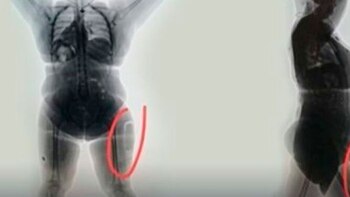

La capturada, una peluquera de 42 años, llevaba 780 gramos de cocaína líquida que estaba "entre la carne y el músculo" de sus muslos, detalló a periodistas el teniente Wilson Silva, comandante de la policía del aeropuerto El Dorado de la capital colombiana.

Los agentes la llevaron a una oficina policial dentro de la terminal aérea y le realizaron un escaneo a su cuerpo, que permitió hallar la droga, que tiene un valor en el mercado de unos 36.000 dólares.